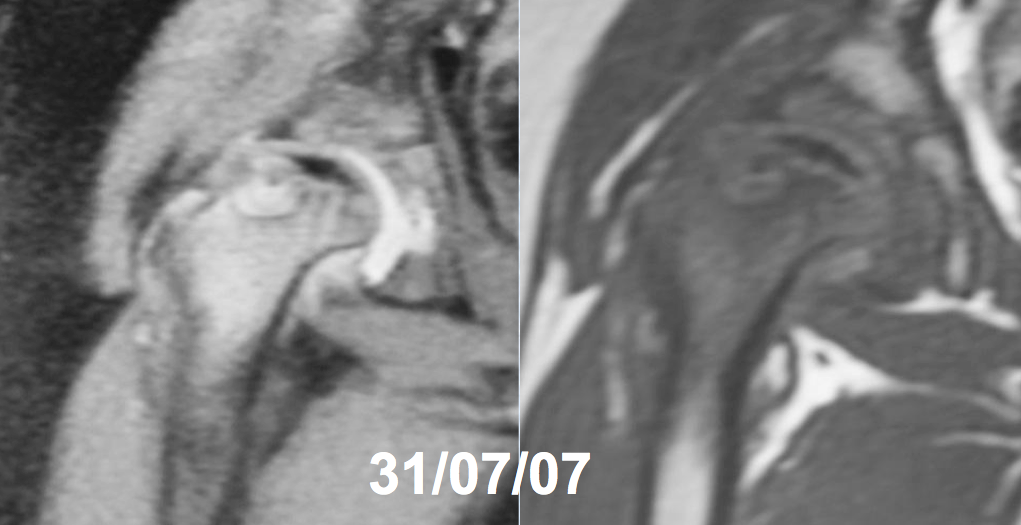

Enfermedad de Legg-Perthes-Calvé recurrente. Descripción de un caso y revisión de la literatura. [Recurrent Legg-Perthes-Calvé disease. A case report and literature review]